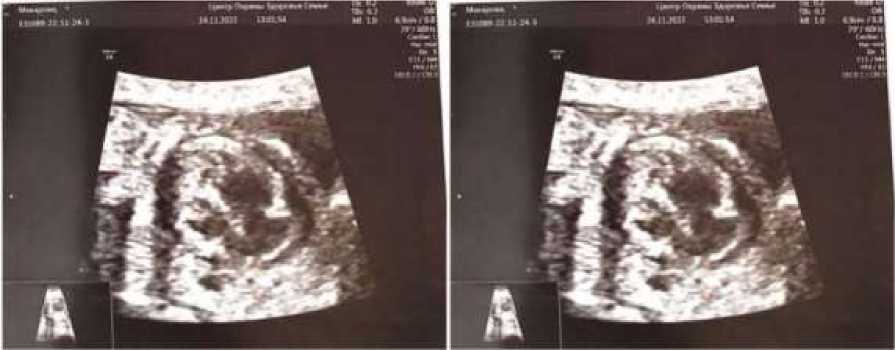

Течение беременности с 17 недель осложнилось гестационной анемией лёгкой степени. При выполнении скринингового ультразвукового исследования на сроке гестации 20 недель и 3 дня выявлены: кардиомегалия (незначительное увеличение правого предсердия); гидроперикард (незначительный). Проведён перинатальный консилиум в сроке 21 неделя и один день. По данным антенатального ультразвукового обследования (АУО) выявлены патологические изменения: врожденный порок сердца (ВПС) плода; двойное отхождение магистральных сосудов от правого желудочка, гипертрофия миокарда правого желудочка, гидроперикард (рис. 1).

Рис. 1. Фотофиксации изображений АУО плода на 20-й неделе беременности